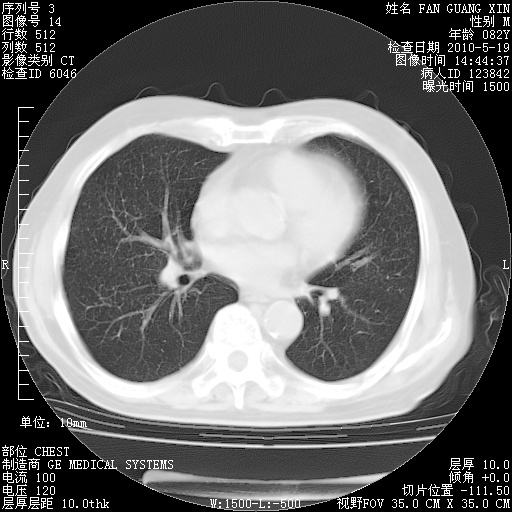

复查肺部CT,明显好转。为什么发热呢?

治疗3周后的肺部CT